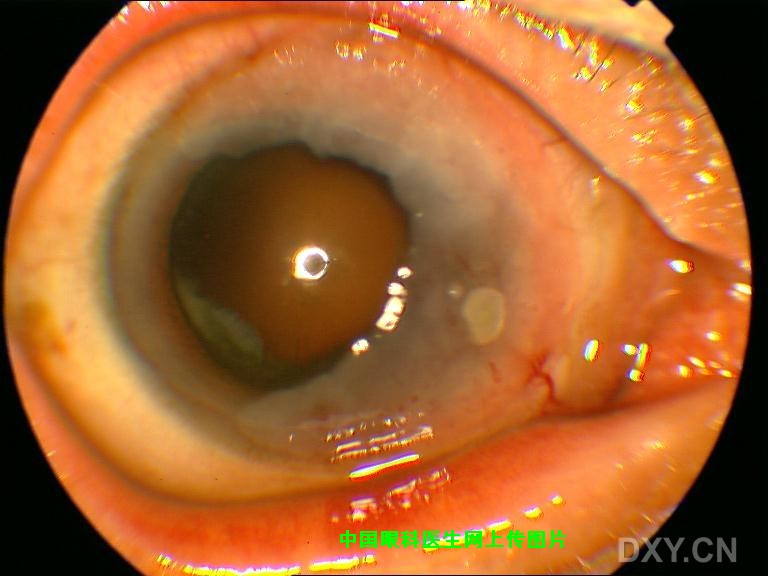

老年男性,左眼略有不适来诊,否认外伤,以前也没有因此就医。 结膜除局部充血外,没有异常增生或隆起;角膜如图,表面没有着色,轻度隆起,KP(-)。病人有酒糟鼻。

裂隙灯下所见

还请大家仔细看图,鼻侧角膜并没有溃疡,更没有局部变薄,而是轻度扁平隆起,再重申一下整个角膜没有染色。 |

该病人的确存在睑板腺功能不良,并且除局部眼药外,也给与口服抗生素。给大家一个线索,查查文献是否为角结膜上皮内上皮癌,又名BOWEN病? |

以下为病人术后2周照片。 病理报告:鳞状上皮乳头样增生伴轻度不典型增生。

非常感谢您所提供的图片,从形态上看,的确与我所报道的病例极为相像,随之而来的是诊断上的困惑,我们诊断为Bowen病(角膜上皮内上皮癌)的主要依据如下: 1.睑裂区角膜缘病变,灰白色半透明隆起,发展缓慢且症状轻微; 2.手术当中非常容易剥离,说明病变没有突破基底膜; 3.当然最有发言权的应该是病理所见(金标准);我曾将病理图片发到丁香园病理讨论区,但回应者不多,看来还是得请咱们眼科特别是病理方面的同行来给大家解释一下该病例的病理图片。 另外如果可能也请您将您所报道病例的术后情况以及病理所见提供给大家。